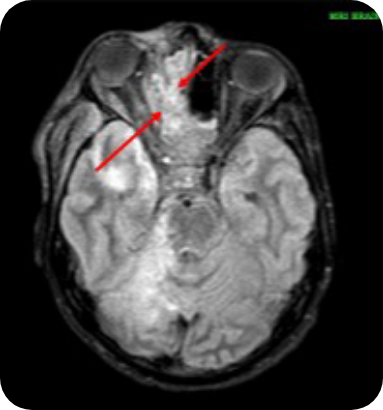

Evidence of stroke in Ahmad's right

superior cerebellum and the right side

of his pons and mid‑brain, due to

blockage of the right superior cerebellar

artery. He also had a blood clot in the

right cavernous sinuses. The scan

showed signs of infection in his right

frontal, ethmoidal, sphenoidal and

maxillary sinuses were also visible

alongside extensive inflammatory

changes in Ahmad's right masticator,

carotid, pre-vertebral visceral spaces

and pre‑maxillary region.

Images supplied with permission of treating clinician.